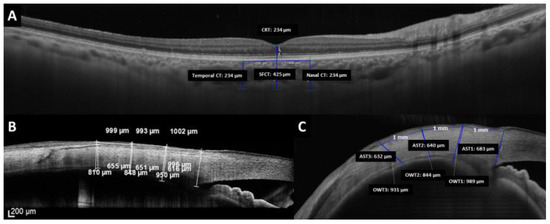

Ocular wall thickness (OWT) refers to the measurement of the complete anterior ocular wall, including conjunctiva, sclera, and ciliary body or choroid (Figure 1). For the AST measurement in the OCT images, the external limit of the sclera can be identified by the deep episcleral vascular plexus, which manifests as a thin hyporeflective region below the conjunctiva-Tenon capsule. The inner boundary is a sharply demarcated line between the hyper-reflective scleral tissue and the hyporeflective ciliary body tissue. OWT and AST were manually measured by the same investigator (ORQ) in a masked fashion in the temporal and nasal quadrants at 1 (OWT1 and AST1), 2 (OWT2 and AST2), and 3 mm (OWT3 and AST3) from the scleral spur.

Figure 1.

Measurements made by optical coherence tomography of the (A) central retinal thickness (CRT), subfoveal choroidal thickness (SFCT), and choroidal thickness at 1 mm nasal and 1 mm temporal from the fovea. (B,C) Measurements of the ocular wall thickness and anterior scleral thickness by the SD-OCT device and SS-OCT device, respectively.

Also, the SFCT, choroidal thickness (CT) at 1 mm nasal and temporal to the fovea, and CRT were measured using the PlexElite device (Figure 1). The reproducibility of the intra and interobserver choroid measurements was studied. To determine intraobserver reproducibility, one expert examiner also took measurements on the same images 2 months after the first measurements. For interobserver reproducibility, measurements were independently made on the images obtained in the initial examination by two expert observers.